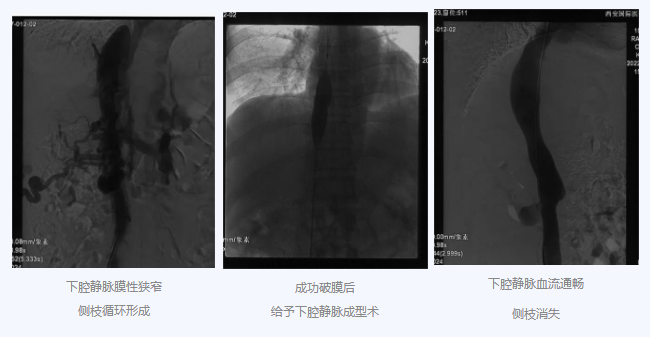

入院后,在韓國宏院長的安排下,臨床經(jīng)驗豐富的醫(yī)師給老謝做了B超、CT 等檢查,結(jié)果顯示:三支肝靜脈近心端閉塞,肝內(nèi)側(cè)枝循環(huán)形成,下腔靜脈近心房入口處隔膜樣狹窄,隨后的DSA血管造影也證實:下腔靜脈狹窄,且有側(cè)枝形成,最終確診困擾老謝20年的疾病為混合型布加綜合征,是一種罕見病。

明確診斷后,韓院長帶領(lǐng)團隊縝密分析老謝的病情,為其制定最佳的治療方案,考慮到老謝的根本病因是下腔靜脈阻塞,介入手術(shù)成為首選治療方法,通過微創(chuàng)介入手術(shù),可準確打通患者的閉塞血管,癥狀迅速緩解。做好充分術(shù)前準備后,為患者行“下腔靜脈成型術(shù)”,精準定位快速貫通,閉塞的下腔靜脈順利開通,手術(shù)圓滿完成。